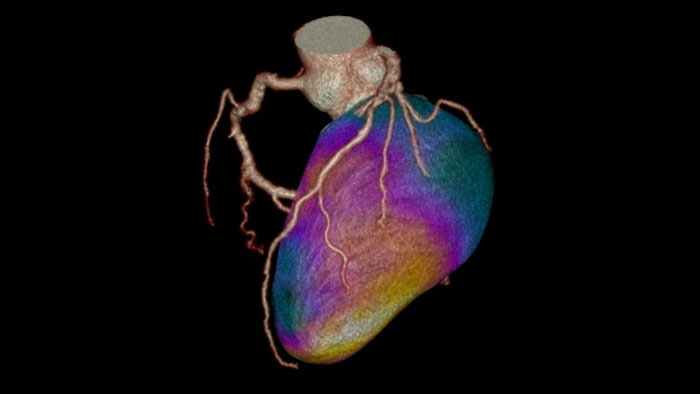

CT Myocardial Defect Assessment

Assessing myocardial defects

Relies on the automatic 3D model-based whole-heart segmentation from the CCA application to provide visual and quantitative assessment of segmented, low-attenuation areas within the left ventricle myocardium from a single, gated cardiac CTA scan.

Benefits

- Volumetric visualization of coronary arteries along with segmentation maps can be displayed as an overlay on top of a 3D myocardial surface.

- Quantitative information includes volume of low attenuation areas within the myocardium and their percentage out of the total myocardial volume.